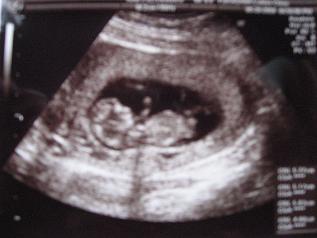

3ヶ月目に入った写真。

胎嚢の形も普通になってるとようやく安心できた1枚です。

胎嚢確認できた日の写真。

胎嚢の形がいびつだから用心しなさいと言われた1枚です。